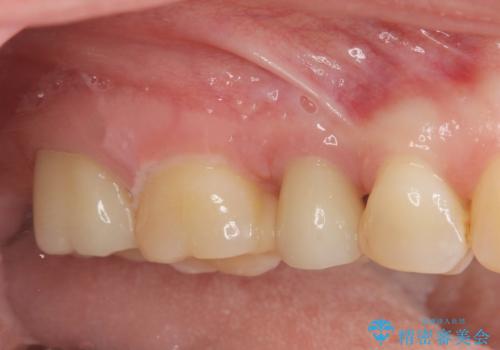

- 44万円 (セラミックインレー×2 ジルコニアクラウン×2)費用は治療当時の料金となります

症状に応じて適切な処置を行ったことで、抜歯を回避し良好な結果を得ることができました。